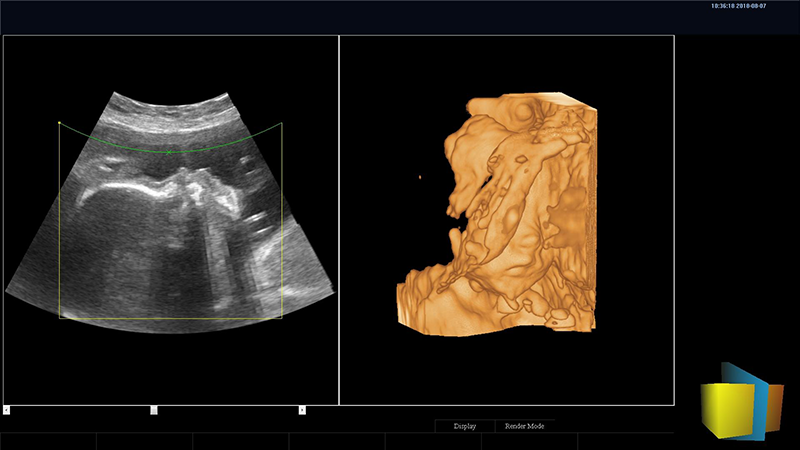

寬景成像(WFOV):擴展掃描視野,實時觀察較大病灶的圖像信息

解剖3M成像技術:解剖3M成像比M型單線模式增加了3條解剖線,測量點角度可調,可得到心臟各個結構更多、更準確的信息,有利于更好的觀察心腔大小及室壁階段性運動的異常情況。